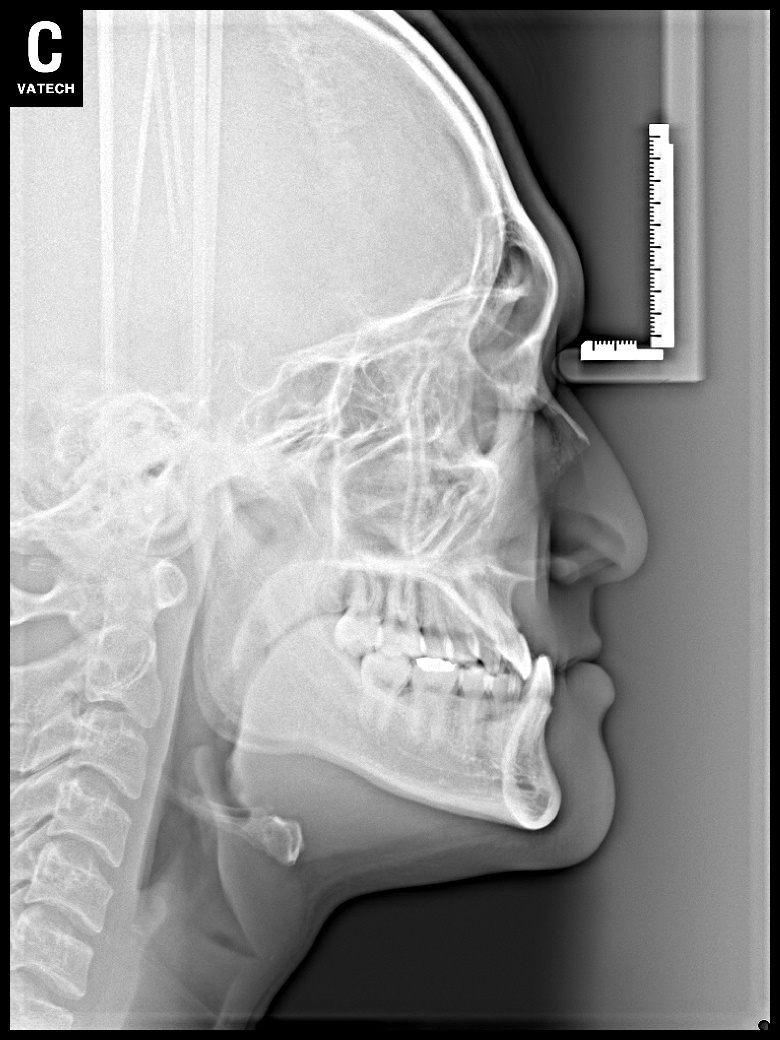

치료 전 사진입니다.